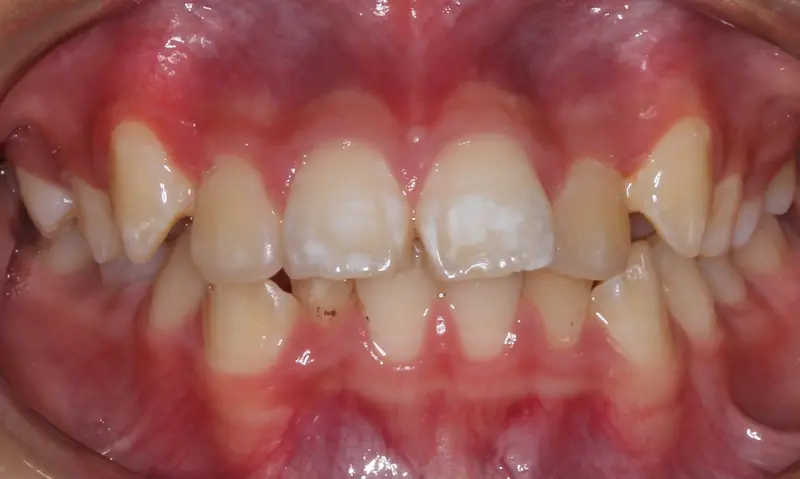

Before treatment: The Expansion Phase

Before

The Diagnosis

Severe crowding with blocked-out permanent teeth. The jaw size was insufficient to accommodate the erupting adult teeth, leading to significant rotation and displacement.

The Engineering

By intervening early, we utilized rapid palatal expansion to develop the arch width. This created the necessary space for the permanent teeth to erupt naturally, avoiding the need for future extractions.